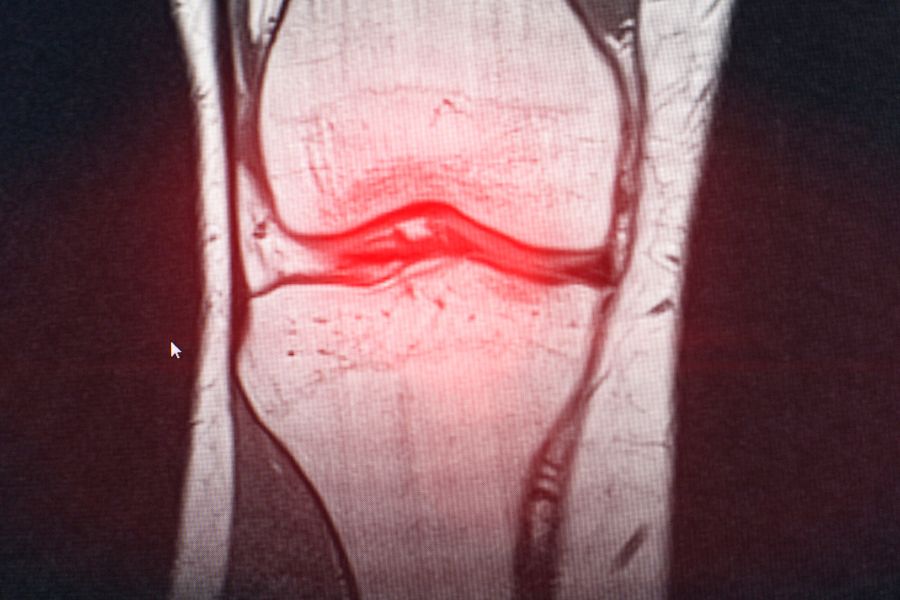

Spor ve Diz Yaralanmaları